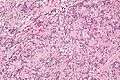

They have a rim of peripheral lymphoid tissue (remnant of a lymph node) and consist of spindle cells with nuclear palisading. Red blood cell extravasation is common and blood vessels surrounded by collagen with (fine) peripheral spokes (amianthoid fibers) are usually seen.[2]

Immunostains for smooth muscle actin and cyclin D1 are characteristically positive. The main histologic differential diagnosis is schwannoma.

Low mag. High mag.

High mag.